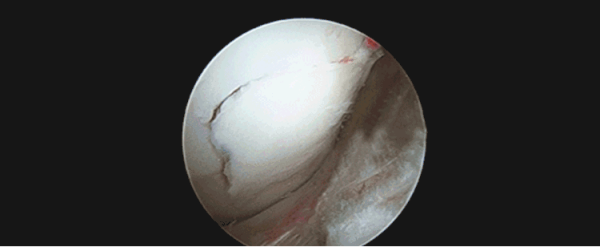

关节软骨损伤